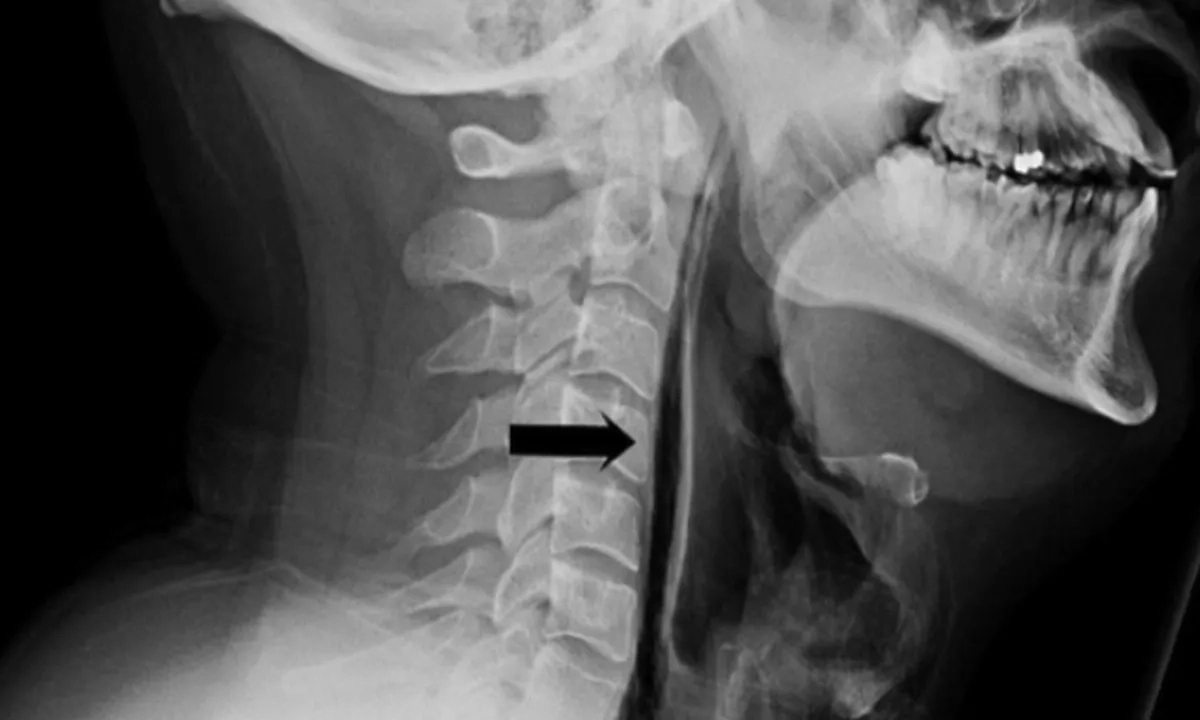

Рентген пациента. Фото © ЦРБ Суоярви

Рентген подтвердил опасное состояние: воздух скопился перед трахеей из-за повреждения пищевода. Врачи предупреждают: попытки подавить чихание могут нанести вред организму, так как создают избыточное давление. Лучше чихать свободно, прикрывая рот платком.